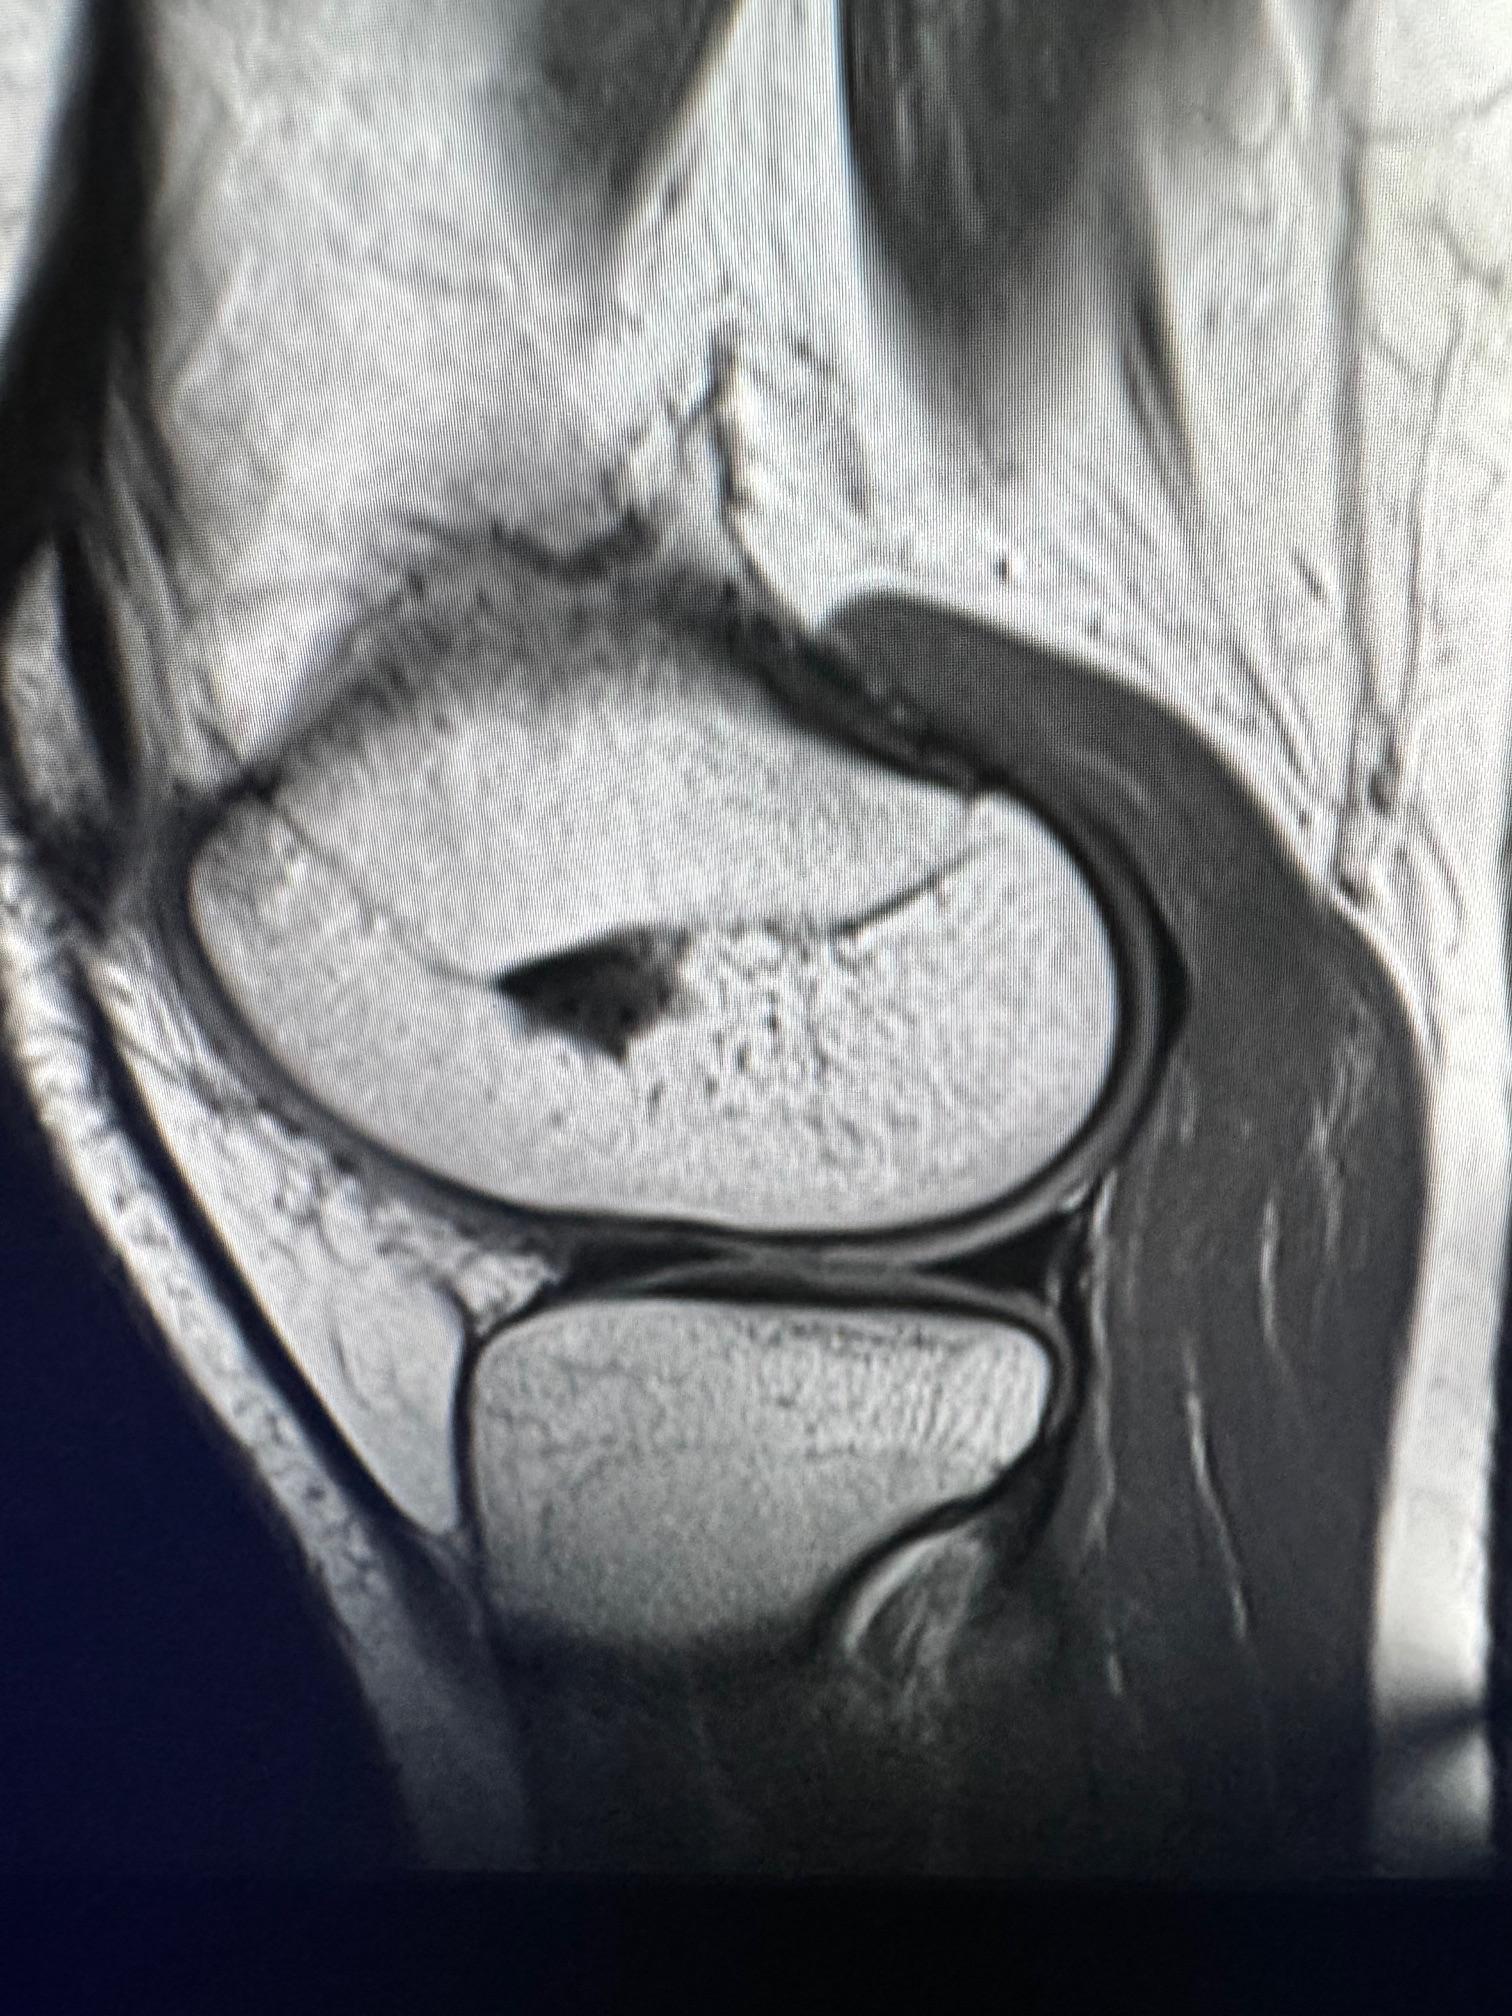

image6